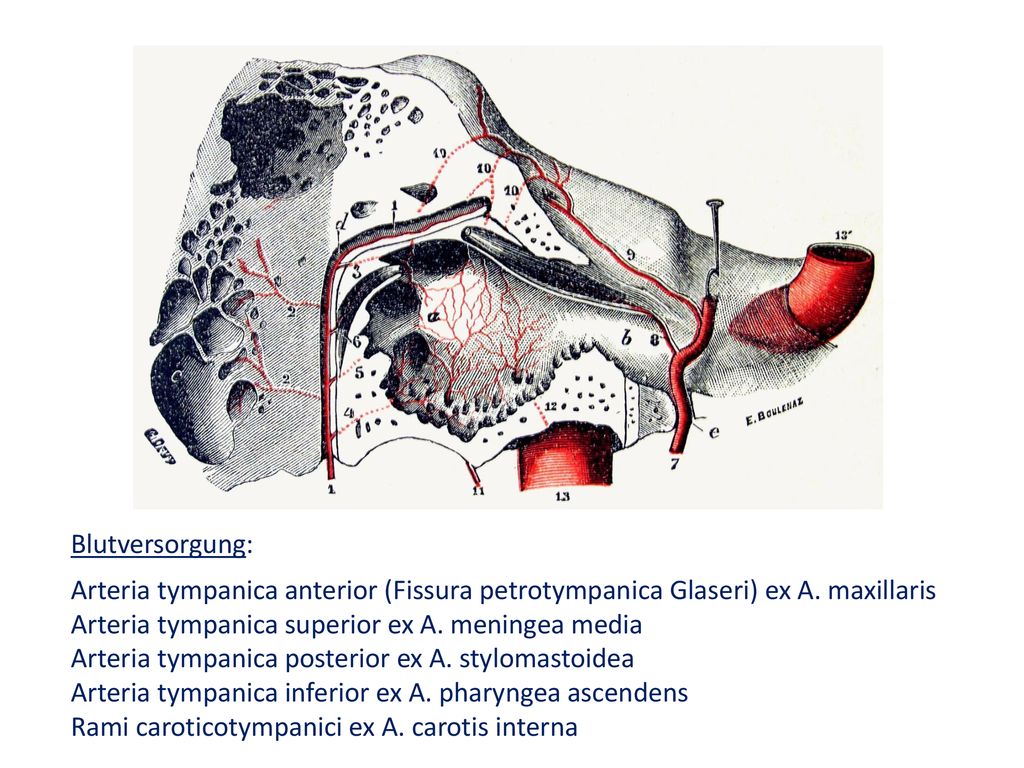

Анатомия и особенности фиссуры петротимпаника